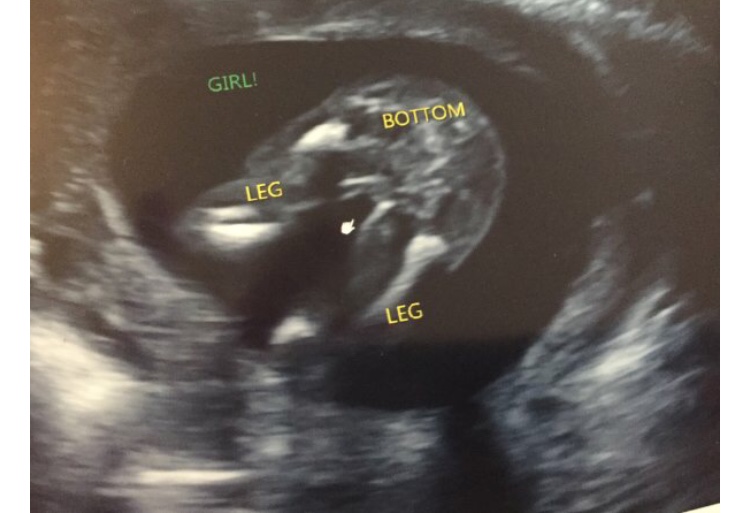

Hi I am new here. Got this potty shot from 16 weeks and 3 days and wondering if I could trust this is really a girl? I want to share my happy but I am afraid that it can still turns out it is a boy?Attachment 41799